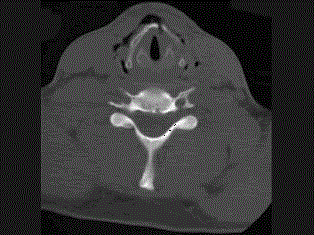

问题 27岁男性,开车外出在高速行驶时翻车,呼吸困难,喉部肿胀,CT检查如图所示,请选择正确的描述或诊断 ( )

选项 A、左侧杓状软骨骨折 B、考虑喉、气管破裂 C、左侧梨状窝软组织肿胀 D、颈部、胸骨下方软组织积气 E、左侧甲状软骨骨折

答案 BCDE